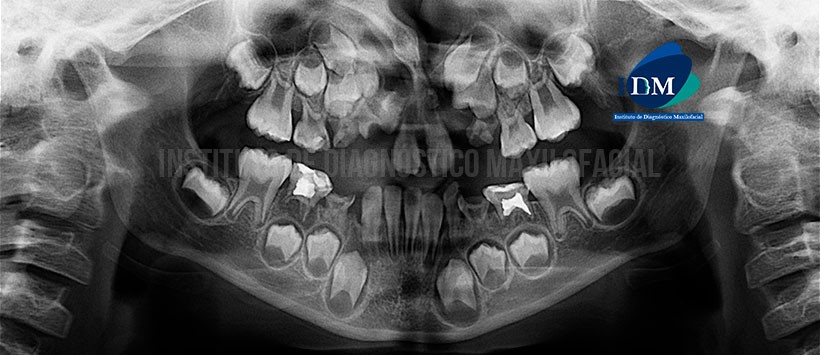

A la evaluación de la radiografía panorámica visualizamos, una falta de espacio para la correcta erupción de las piezas permanentes en ambos maxilares, desviación del septum nasal hacia lado derecho, una aparente pérdida de continuidad por parte del hueso nasopalatino en relación a ambas arcadas dentarias del maxilar superior, presencia de dos piezas supernumerarias en dicha región, múltiples piezas deciduas con restauraciones coronarias y lesiones cariosas. (Figura 1)